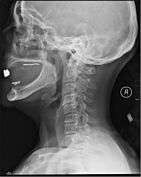

Diagnosis

A radiographic evaluation using an X-ray, CT scan, or MRI can determine if there is damage to the spinal column and where it is located.[6] X-rays are commonly available[64] and can detect instability or misalignment of the spinal column, but do not give very detailed images and can miss injuries to the spinal cord or displacement of ligaments or disks that do not have accompanying spinal column damage.[6] Thus when X-ray findings are normal but SCI is still suspected due to pain or SCI symptoms, CT or MRI scans are used.[64] CT gives greater detail than X-rays, but exposes the patient to more radiation,[65] and it still does not give images of the spinal cord or ligaments; MRI shows body structures in the greatest detail.[6] Thus it is the standard for anyone who has neurological deficits found in SCI or is thought to have an unstable spinal column injury.[66]